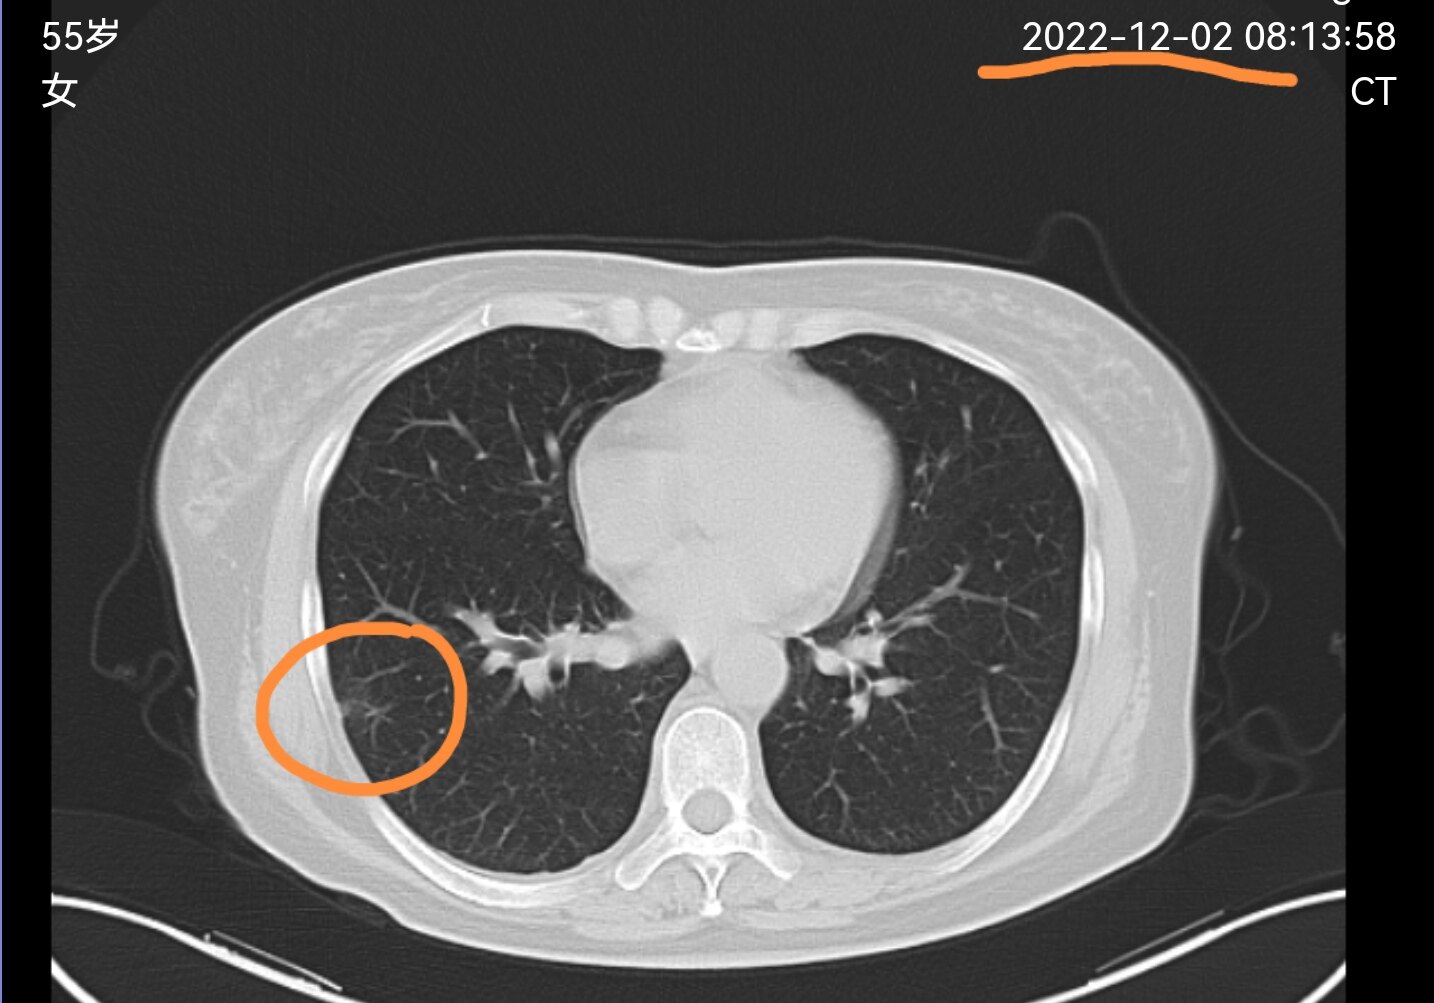

有一位东北的同行在线上门诊平台联系到我,把她这两个月拍的胸部CT电子图像发给了我。她10月底第一次拍片子时,发现了肺部靠近胸膜有一个结节,当地医生给安排了抗炎治疗,前两天她又复查了个CT,看到结节有变化了,想让我看一下结节的性质,还需不需要做手术?

从她第一次拍过来的片子看,这个肺结节首先考虑是一个炎性病变,当地医生安排抗炎治疗是完全正确的,五个星期之后再次复查,看到这一位置的这个结节较前明显消散,证实这是一个炎性结节,肯定不需要手术了。

通过我们同行的这个病例,大家可以知道,第一,有些肺结节是可以通过抗炎治疗变小和消散的,第二,要经过几个星期再复查片子,不要刚抗炎完就马上复查片子,要给肺结节一个吸收的过程。